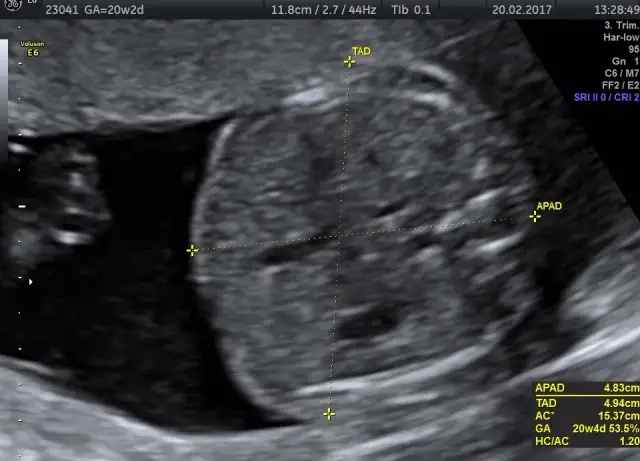

Poznaj, jak wyglądają badania połówkowe, ich etapy oraz co warto wiedzieć przed USG. Zyskaj pewność i spokój w trakcie ciąży!